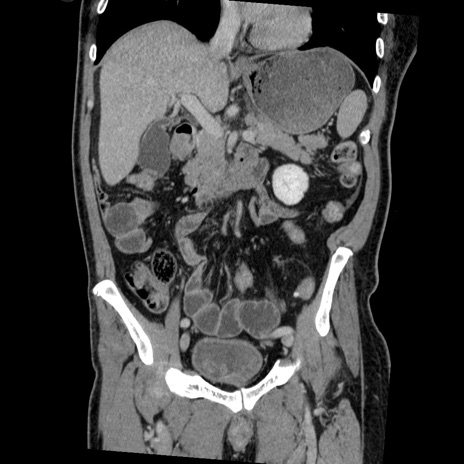

症例22(冠状断像)

【症例】50歳代男性

【主訴】腹痛

【現病歴】AVMからの被殻出血のため回復期リハ病棟入院中。 本日午後3時頃急に下腹部痛が出現した。

【既往歴】AVM、被殻出血、虫垂炎、高血圧

【身体所見】意識晴明、左半身不全麻痺、会話の理解は良好、36.5°C、腹部:膨隆、全体に板状硬、下腹部正中に圧痛点あり、反跳痛-、筋性防御不明、右下腹部にope scar

【データ】WBC 9400、CRP 0.06